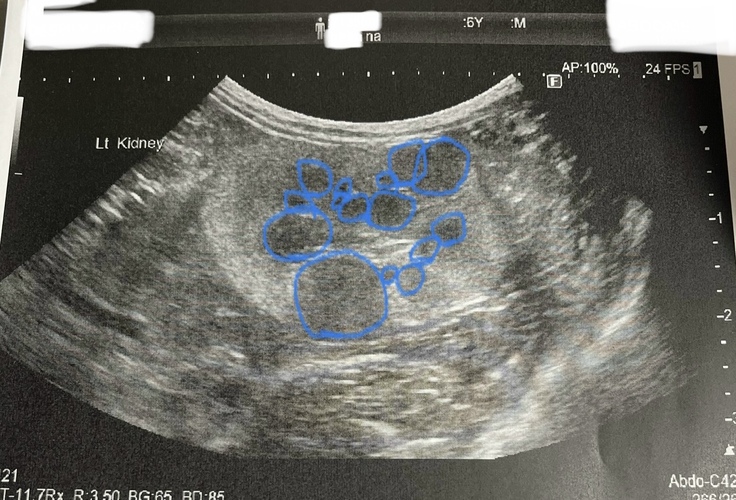

なっちゃんの左側の腎臓には複数の腫瘍があります。

↑画像は腎臓の一部分で、青丸が腫瘍 です。

右側の腎臓は萎縮していて、ほとんど機能していません。

腫瘍がある左の腎臓を摘出すると、排尿できなくなり亡くなってしまうそうです。

したがって手術はできません。